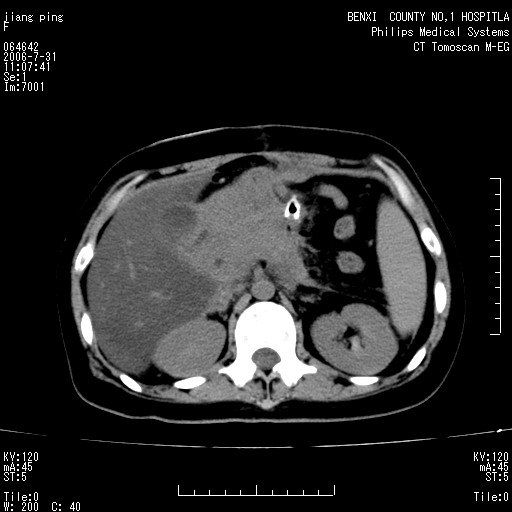

以下是引用晓杰在2006-8-1 9:01:00的发言:[br]支持营养不良导致脂肪肝。[br]胰头增大界限不清,考虑为胰腺炎破坏十二指肠粘膜、肠壁增厚、肠腔狭窄,并与胰头粘连所致

以下是引用jiajie在2006-7-31 20:34:00的发言:[br]支持营养不良导致脂肪肝。[br]胰头增大界限不清,考虑为胰腺炎破坏十二指肠粘膜、肠壁增厚、肠腔狭窄,并与胰头粘连所致。